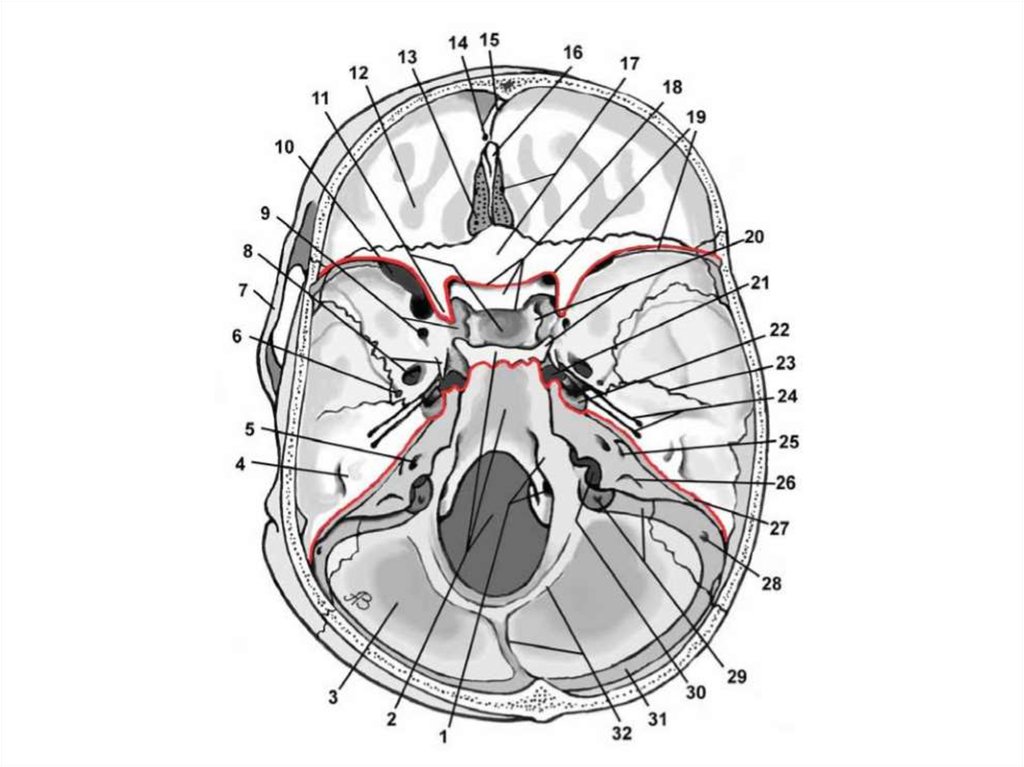

СРЕДНЯЯ ЧЕРЕПНАЯ ЯМКА (СЧЯ)

СЧЯ образована:

• телом и крыльями клиновидной кости;

• передненижними отделами чешуйчатой части и

передней поверхности пирамиды височной кости.

СЧЯ

медиальная часть

латеральная часть

Медиальная часть СЧЯ:

• внутренние отверстия зрительных каналов;

• предперекрестная борозда;

• турецкое седло;

• гипофизарная ямка, ограниченная с боков

бороздами внутренних артерий.

ЗАДНЯЯ ЧЕРЕПНАЯ ЯМКА (ЗЧЯ)

ЗЧЯ расположена между пирамидами височных

костей, чешуей затылочной кости и скатом.

В ней лежат ствол мозга и мозжечок.

• Внутренний затылочный выступ внутренний

затылочный гребень;

• Мозжечковые ямки;

• Борозда поперечного синуса;

• Борозда сигмовидного выступа;

• Скат;

• Яремный бугорок.

ОТВЕРСТИЯ ЗЧЯ

БОЛЬШОЕ ЗАТЫЛОЧНОЕ ОТВЕРСТИЕ

Содержимое:

позвоночные артерии;

передние и задние менингеальные ветви позвоночной

артерии;

спинномозговые корешки добавочного нерва;

передние и задние спинномозговые артерии.

СОСЦЕВИДНОЕ ОТВЕРСТИЕ

МЫЩЕЛКОВЫЙ КАНАЛ

ЯРЕМНЫЙ КАНАЛ

каменистая часть

сигмовидная часть

невральная часть